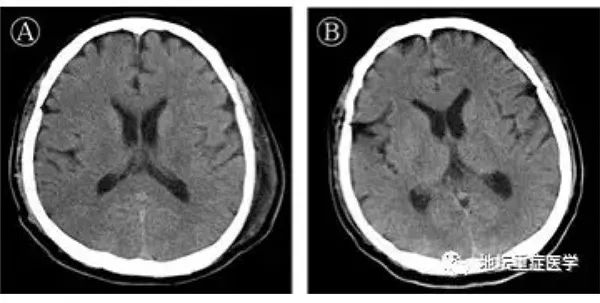

已证实新冠病毒攻击中枢神经系统也是在昨天(3月4日),首都医科大学附属北京地坛医院公布,一名治愈出院的新冠肺炎合并脑炎患者,出现意识障碍,是全球报道的首例中枢神经系统受攻击病例。

中枢性神经系统受损,主要表现为头昏,头痛和神经系统机能障碍三方面。 而人类中枢神经,是让我们健康生活的基础。如果运动性语言中枢受损,患者与发音有关的肌肉虽未瘫痪,却丧失了说话的能力;听性语言中枢受损,患者能讲话,但混乱而割裂。